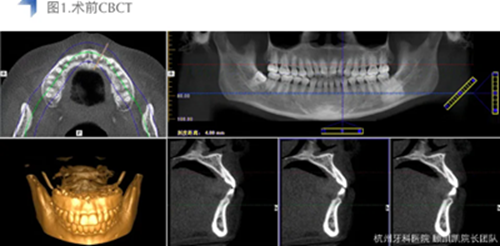

接診后口內(nèi)檢查12近中鄰面較大面積齲齒,探不適,叩無不適,冷熱測試同時對照牙及臨牙,BOP+,捫診(-),未有異常松動度。術前CBCT檢查如下圖,未見明顯根尖周透射影。